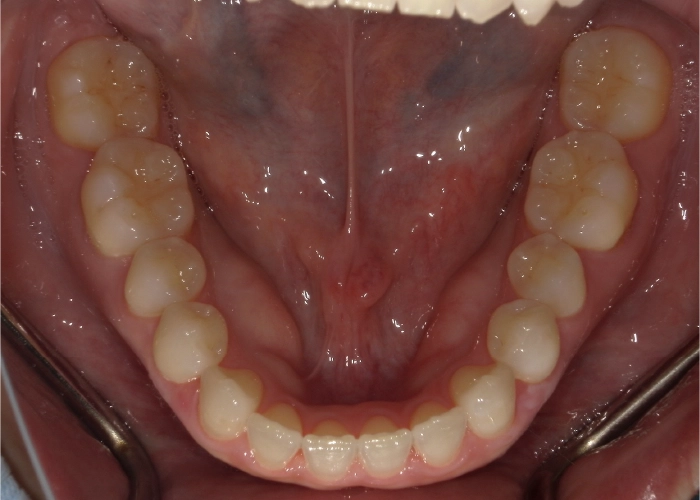

全体的ながたつきを改善したい